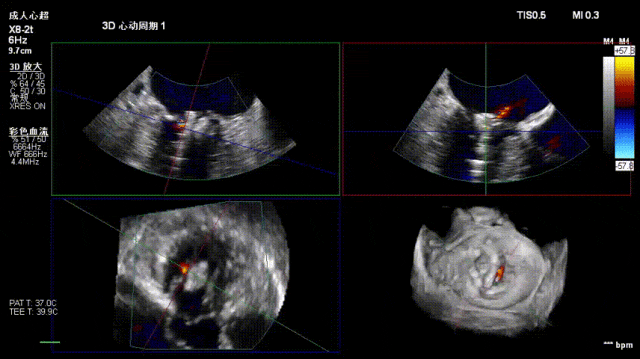

术后复查超声心动图显示:二尖瓣轻度返流,三尖瓣中度返流,二尖瓣可见金属夹回声,启闭正常;各心室大小正常,升主动脉不宽,主瓣回声增强,启闭良好;二尖瓣舒张期峰值流速1.4 m/s,功能面积2.1 cm²,跨瓣平均压差约4 mmHg。

术后心功能改善明显:LVdD 46mm,FS 33%,LA 45mm,LVDs 31mm,LVEF 62%。

患者术后症状明显缓解,胸闷和喘憋改善,恢复情况良好。